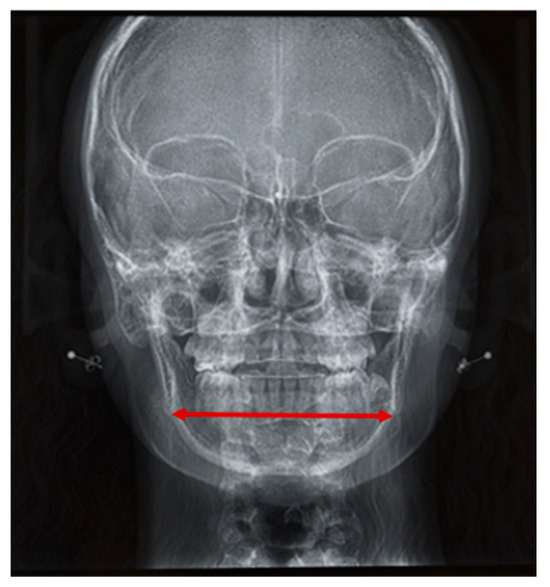

Background: The aims of the study were to describe facial morphology and analyze facial growth in adolescents with Robin sequence (RS) or Stickler syndrome. Methods: The facial morphology, mandibular size, and facial growth of 69 adolescents (ages 12–18) with RS were analyzed using existing cephalometric radiographs (n = 37) and photographs (n = 69). All participants were followed in our institution since birth. None underwent growth-modifying treatment for micrognathia during infancy, but all had conservative orthodontic treatment during adolescence. Results: Cross-sectional cephalometric analysis according to Tweed revealed differences in RS adolescents as compared with reference values, such as a proportionate retrusion of both jaws, as indicated by decreased SNA and SNB angles (p < 0.05). This finding was mostly associated with skeletal Class I (62.2%) and a vertical facial pattern as indicated by increased FMA and CoGoMe angles (p < 0.05). In Delaire’s analysis, patients showed decreased maxillary, maxillary alveolar (p < 0.05), and mandibular body territories (p > 0.05) but increased ramus (p > 0.05) and nasopremaxillary territories (p < 0.05). According to Ricketts’ analysis, mandibular width was decreased in half of our patients (p > 0.05). The mandibles were harmoniously downsized before and after the growth spurt (p < 0.05); however, they exhibited greater growth velocities than controls. A long-term study during puberty revealed an increase in SNB angles and a decrease in ANB angles (both p < 0.05), which improved the maxillomandibular relationship. Additionally, the vertical facial pattern attenuated (FMA, SNGoGn, and CoGoMe angles decreased; p > 0.05). On cross-sectional photographic analysis, 33.3% of patients had an orthofrontal (straight), 59.4% a cisfrontal (convex), and 7.3% a transfrontal (concave) profile. Their vertical facial proportions were normal. In the subjective profile analysis, most patients (approximately 84%) had good or acceptable profiles, with no major deficit of chin projection. The initial degree of neonatal retrognathia and type of cleft palate surgery did not affect major skeletal parameters (p > 0.05). However, the degree of neonatal functional impairment affected the vertical parameters (SNGoGn, FMA angle; p < 0.05). Conclusions: Overall, RS patients presented a bi-retrognathic profile, a normal jaw relationship, and a tendency toward a vertical growth pattern. Partial mandibular catch-up growth occurred during the pubertal growth spurt. The degree of neonatal retrognathia does not predict further mandibular growth. Full article